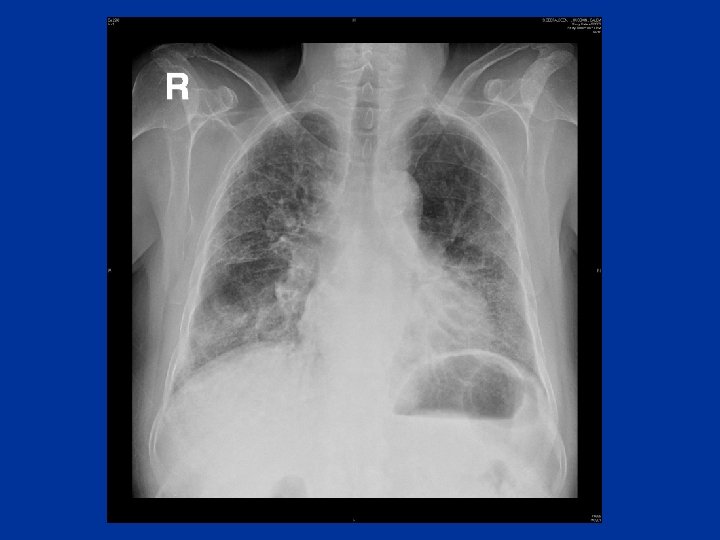

Chronic dyspnea • Major causes: Asthma COPD Bronchiectasis Interstitial lung disease Heart failure or cardiomyopathy

Evaluation • • • History& physical exam CXR PFTS Oximetry Echocardiogram CT-lungs - I. L. D _ Bronchiectasis - Occult emphysema - Chronic thromboembolic dis. • Cardiopulmonary exercise